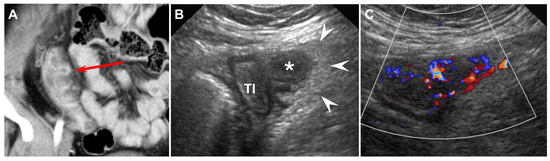

Figure 1. Forty-eight-year-old female (patient #8) with acute ileal diverticulitis. (A) Coronal reformatted enhanced CT scan reveals an outpouching diverticular sac (red arrow) connecting to the terminal ileum and mild ileal wall thickening. (B) US scan with C8-5 convex transducer demonstrates a homogeneous hypoechoic diverticular sac (*) connecting to the terminal ileum (TI), surrounding hyperechoic inflamed fat (arrowheads), and mild wall thickening of terminal ileum (TI). (C) Color Doppler imaging shows increased color flow to the diverticular wall and surrounding inflamed fat.

The CT findings for acute ileal diverticulitis are summarized in Table 2. All 17 patients had ileal diverticulum along the mesenteric border. Inflamed diverticulum was seen in 16 patients (94.1%) (Figure 1). The remaining patient did not have an inflamed diverticulum at the center of ileal wall thickening with abscess; however, adjacent ileal diverticula supported the diagnosis of acute ileal diverticulitis with perforation, and barium study after 1 month demonstrated two ileal diverticula along the mesenteric border (Figure 2). Three patients had radiodense fecalith within the inflamed diverticulum (Figure 3). All 17 patients had mesenteric fat infiltration with varying degrees and ileal wall thickening. Five patients (29.4%) were diagnosed with perforated ileal diverticulitis, which had the following findings: abscess (n = 2) (Figure 2), extraluminal fluid with air (n = 3) (Figure 4), and/or focal defect in the diverticular sac (n = 2) (Figure 5). Mesenteric venous gas (Figure 4) and mesenteric venous thrombosis were seen in two patients (11.8%), respectively.

The US findings for acute ileal diverticulitis are summarized in Table 3. All patients showed outpouching inflamed diverticular sac connecting to the ileum, peridiverticular inflamed fat presenting as hyperechoic fat around the diverticulum, and increased color flow to the diverticulum and surrounding inflamed fat on CDI (Figure 1). The inflamed diverticulum exhibited variable echogenicity (Figure 2 and Figure 3). Like CT findings, eight patients had a single diverticulum and nine patients had multiple diverticula. Unlike CT, US examinations diagnosed perforated ileal diverticulitis in seven patients. The findings indicated that five patients had both abscess and extraluminal air bubble (Figure 4 and Figure 5), one patient had only extraluminal air bubble (Figure 6), and one patient had only abscess.